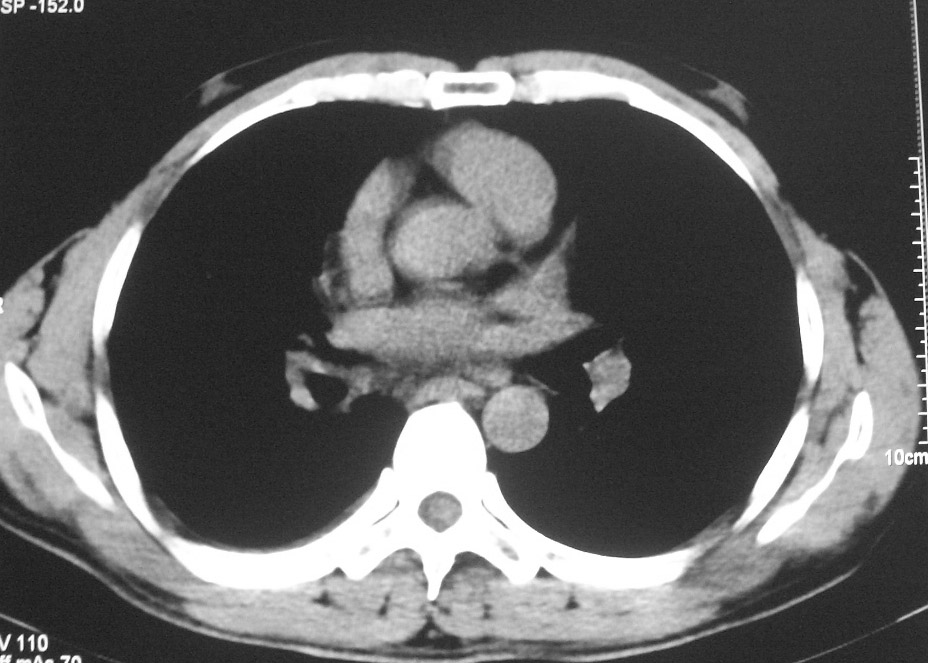

标题: CT5485:[原创]肺部占位请讨论

右肺上叶中央型肺癌并上叶肺不张、纵隔淋巴结肿大

右上叶支气管后壁明显增厚,支持右肺上叶中央型肺癌伴右上叶肺不张、纵隔淋巴结肿大。

右上叶支气管后壁明显增厚,支持右肺上叶中央型肺癌伴右上叶肺不张、纵隔淋巴结肿大。建议支气管镜检查。

右上叶支气管开口变窄,纵隔见肿大的淋巴结。支持右上叶中心型肺癌并右上叶不张纵隔淋巴结肿大。

右肺上叶中央型肺癌并上叶肺不张、纵隔淋巴结肿大.右侧少量胸腔积液。

右上肺中心型肺癌并肺不张,纵膈淋巴结肿大。右侧少量胸腔积液。

右肺上叶支气管后壁增厚,呈鼠尾状狭窄,纵隔内未见明显增大的淋巴结影,考虑为中央型肺癌伴右上肺不张